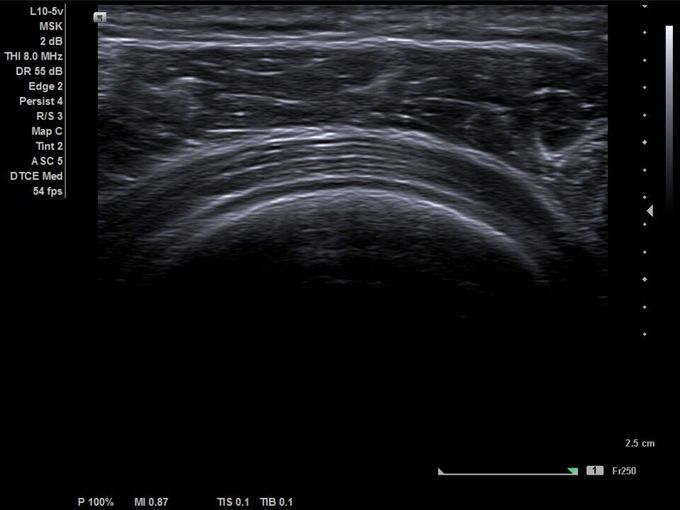

Кроме новой техники, можно заказать восстановленные медицинские системы: ультразвуковые сканеры, томографы, флюороскопы, ангиографы и хирургические установки С-дуга.